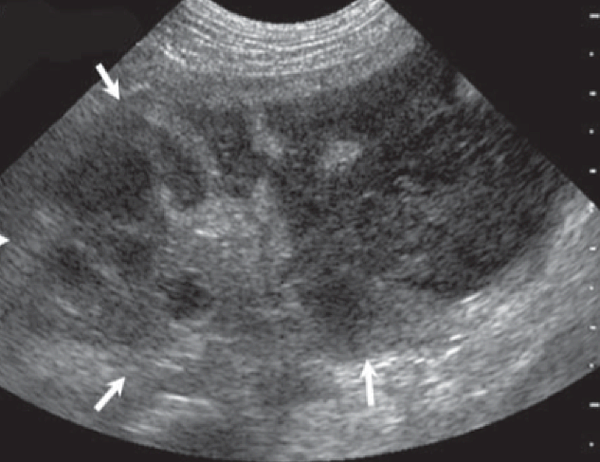

由超音波檢查攝護腺時,良性攝護腺肥大增生時,攝護腺會對稱性且均值地曾厚,但如果出現囊泡樣增生、外型不對稱、結構改變,如下圖,可能需要藉由細針採樣,將部分攝護腺細胞透過顯微鏡觀察型態,以區分良性增生、惡性增生、感染等情形。

圖二、攝護腺炎